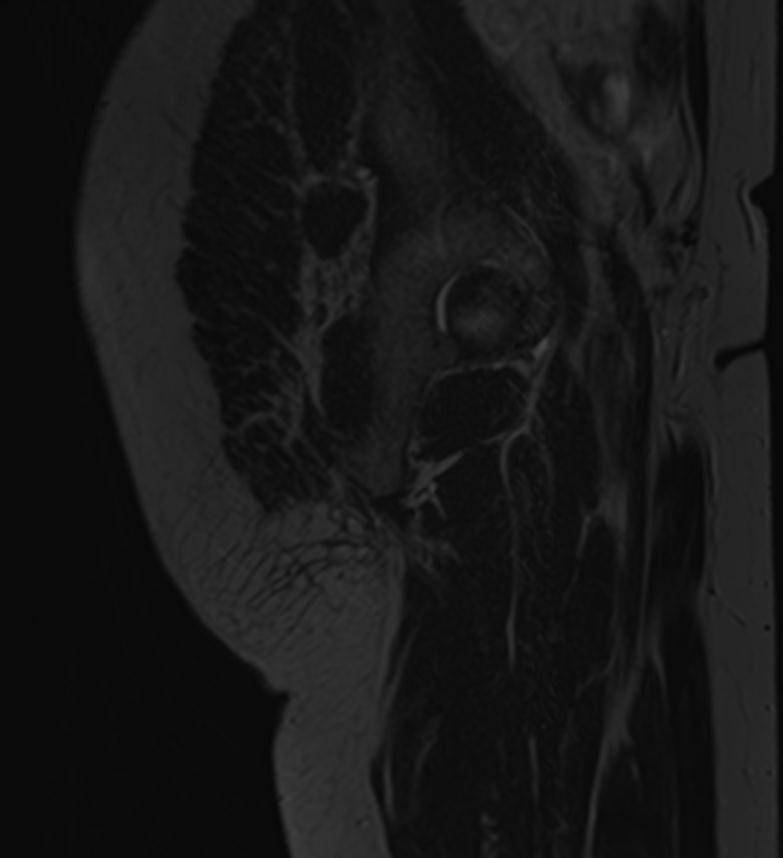

Ягодичная область включает в себя большую, среднюю, малую ягодичные мышцы, грушевидные мышцы, мышечные фасции, межфасциальные клетчаточные пространства, связки, нервные волокна, половой сосудисто-нервный пучок, лимфоузлы и лимфатические протоки. Ягодичные мышцы участвуют в движениях нижних конечностей и обеспечивают устойчивость тела в вертикальном положении.

Чаще всего ягодичная область подвержена развитию воспалительных заболеваний, травматических повреждений и опухолевых процессов. Наиболее эффективным способом диагностики патологии мягких тканей ягодичной области является магнитно-резонансная томография. При применении данного метода не используется вредное ионизирующее излучение, как при обычном рентгене или КТ, при этом МРТ дает наибольшую информацию о состоянии мягкотканных структур, выявляя патологические очаги размером от 1 мм.

- Закрытые и открытые травматические повреждения (ушибы, гематомы, растяжения связок, разрывы мышц, повреждения сосудов и нервов).

- Воспалительные заболевания ягодичной области вследствие травм, нагноения гематом, после проведения инъекций (абсцессы, флегмоны ягодичной области).